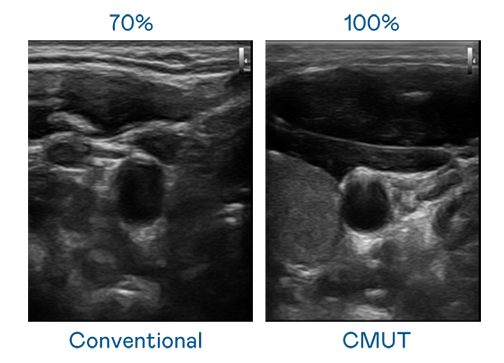

CMUT 技術是一種用電容式微機電元件來產生超音波訊號的技術。與傳統 PZT 壓電式技術相比,CMUT 頻寬增加 30%,更寬頻的超音波訊號讓影像解析度大幅提升,是實現高影像品質醫療超音波掃描、促進精準醫療發展的關鍵技術。

大頻寬帶來超清晰影像

超音波影像的解析度高低,首先取決於探頭能發出的訊號頻寬。九游会ag CMUT 可提供高清晰的超音波訊號,提供高頻寬、高靈敏度、影像紋理細節更高的超音波影像,協助醫護人員縮短影像判讀時間及利用精準的醫療影像進行診斷。